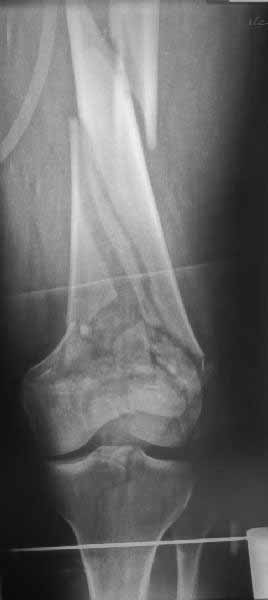

Представленный снимок не дает полную информацию. Там вроде простой перелом, но на самом деле, кроме смещенного (латерального, возможно медиального?) мыщелка на второй проекции имеется медиальный короткий дистальный фрагмент в флексии. Надо было сделать прямой снимок с захватом малоберцовой, который ориентировал бы стороны. Без КТ обычный снимок в дистракции поможет разобраться в топографии фрагментов.

Во время фиксации надо соблюдать осторожность, особенно с коротким фрагментом на другой стороне. Обычно на прямой проекции трудно заметить флексионную деформацию мыщелка и упускается адекватная фиксация. Без пластины винты не смогут удержать, и мыщелок на второй стороне может сместиться. Для фиксации надо развернуть мыщелок и удержать винтами. Качество межмыщелковой репозиции надо проконтролировать артротомией. Из всех доступов только передне-латеральный доступ (Swashbuckler) даст обзор для ревизии качества фиксации, который в будущем может быть использован для артропластики.

Кстати, из вашего снимка, если отмечены вашим рентгенологом правильно, тогда получается снимок левого колена, и, соответственно, длинный переходящий в диафиз мыщелковый фрагмент находится медиально. Если так, тогда меняется сценарий фиксации!!!

Сразу не обратил ваше внимание именно на это, что сломаны оба мыщелка, и больший является именно медиальным мыщелком, а пластины ставятся по латеральной стороне, соответственно, в этом медиальном мыщелке от пластины останутся только концы винтов, которые не обеспечат достаточной фиксации мыщелка.

И не обратите, коллега, пока не сделаете четкие анфасные снимки (лучше с дистракцией) где будет четко визуализироваться малоберцовая кость. Думается, что и КТ здесь будет уместно, дабы не пропустить возможное флексионное повреждение (перелом Hoffa).